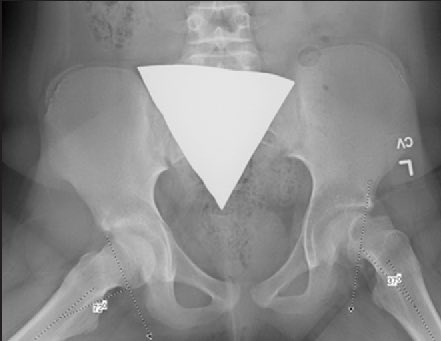

1️⃣بالرغم من كفاءة فنيي وأخصائيي الأشعة إلا أن الواقي قد يوضع في مكان خاطئ ويغطي منطقة مهمة في التشخيص.

وفي هذه الحالة قد يحتاج الأخصائي لإعادة الفحص من جديد 🙃

الصورة مثال لأحد هذه الحالات